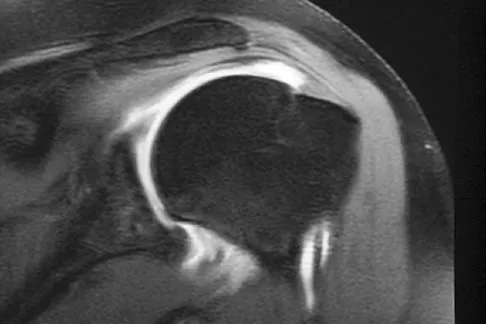

An 18-month-old boy with obstetric brachial plexus palsy is being evaluated for limited right shoulder motion. Physical therapy for the past 6 months has failed to result in improvement of the contracture. Which of the following studies is necessary prior to any shoulder reconstruction?